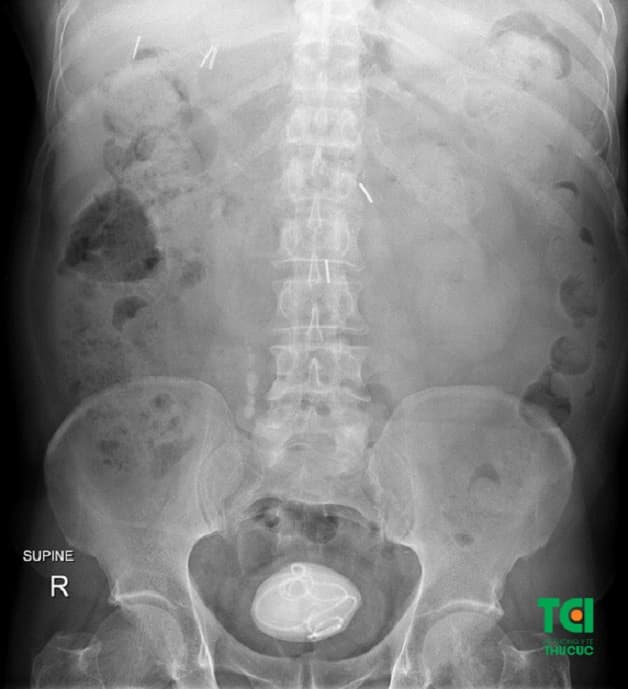

Sỏi bàng quang là một dạng chất rắn kết tủa nằm tại bàng quang

Bệnh nhân mắc sỏi bàng quang kích thước lớn

Nội soi ngược dòng tán sỏi bàng quang kích thước 10mm